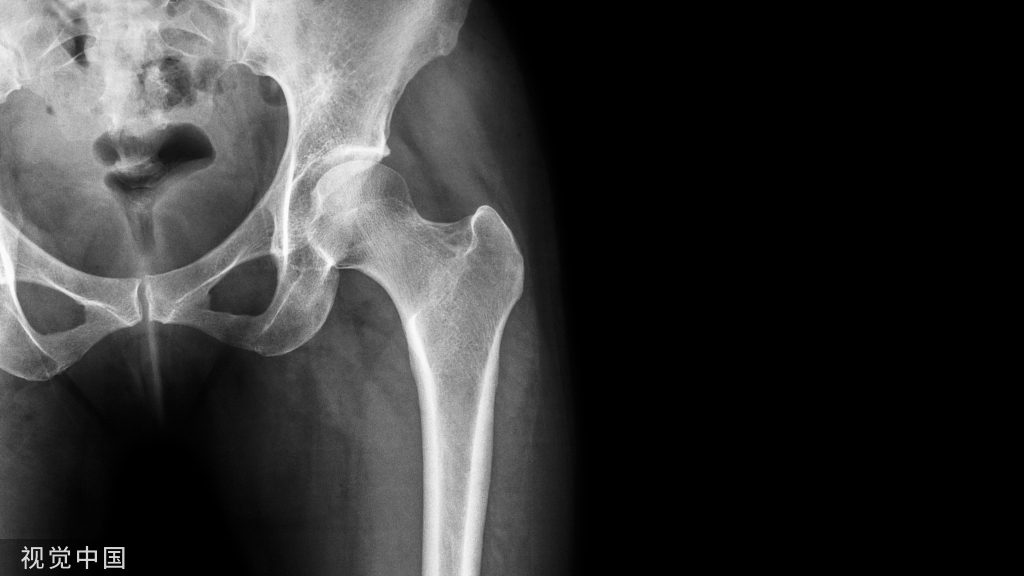

如果仅存在单纯的前后移位,后方没有绞索,也可应用以下方法

1、远端植入椎弓根螺钉,保留一些距离2、近端植入到底的椎弓根螺钉

3、若存在左右侧的位移,可让螺钉的开口侧面向近端脱位的一侧4、将棒塑性有一些弧度,先锁定远端后,利用棒的弹性来逐渐锁定近端达到复位

5、然后再将远端的钉子与棒逐个分离后拧入适当的深度,最后更换更合适的棒进行锁定